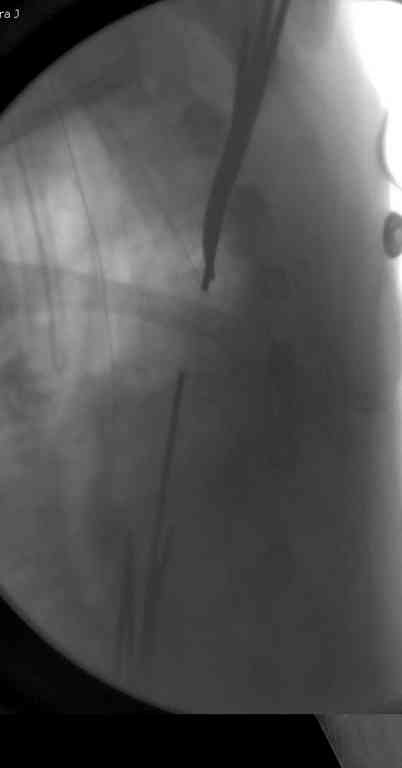

Сделали напряженными спицами по методике А.Ф.Лазарева со товарищи Репозиция сделана спицевым дистрактором, проксимальная спица была проведена в полскости деформации перпендикулярно оси наклонившейся головки. Получилось все довольно легко. Спицы малость покороче можно было сделать, ну да удалять потом легче будет.

Картинка в приложении.

Очень даже неплохо получилось. Молодцы! Лучше чем на 3D "репозиции".